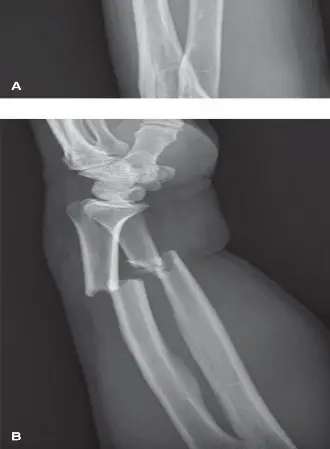

الأشعة السينية X-ray

تُعد الأشعة السينية هي الخطوة الأولى والأساسية في تشخيص كسور الساعد ومشاكل تقوس الكعبرة.

- صور متعددة الزوايا: يتم أخذ صور بالأشعة السينية من زوايا مختلفة (أمامية خلفية وجانبية) للساعد، بما في ذلك المرفق والرسغ، لتقييم الكسر بشكل كامل.

- تقييم التقوس والطول: تساعد الأشعة السينية في تحديد موقع الكسر، ودرجة الإزاحة، وأي قصر في العظم، وأي تغيير في تقوس الكعبرة.